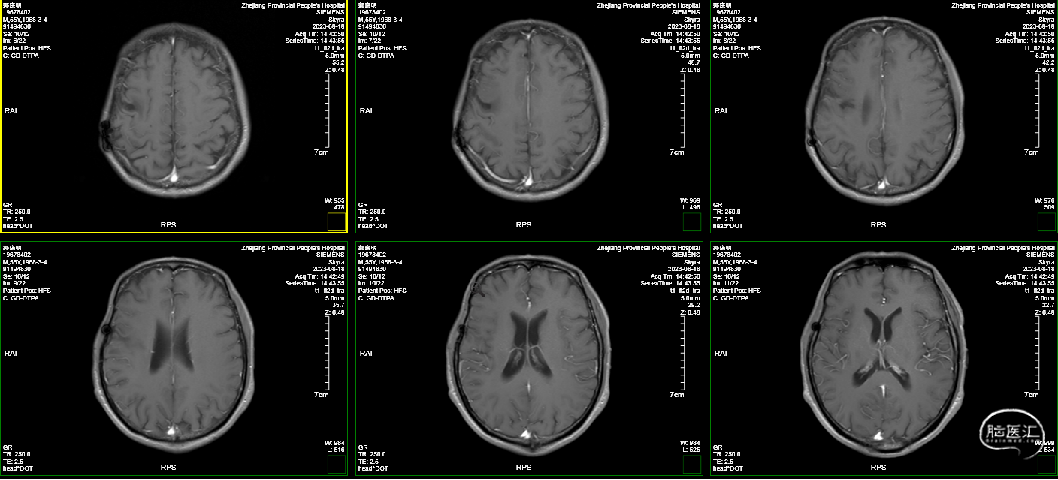

术后一年复查